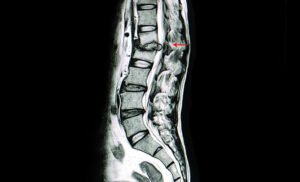

MRI showing Tuberculous destruction of the spine. Also referred to as Pott’s spine

Infections like Pott’s spine (tuberculosis affecting the spine) and tumors in the spine can lead to low back pain. Treatment varies and may include antibiotics for infections or surgery for tumor removal.